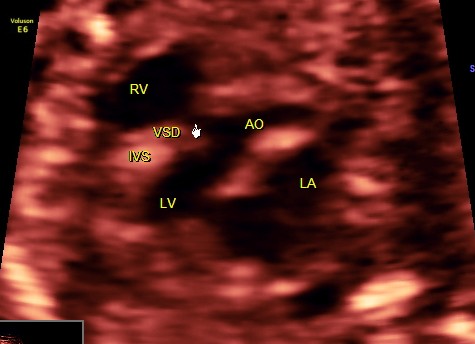

Fetal echocardiography can pick up VSD .

This was a 21 year old primi with h/o consanguinity ; Gestational age at the time of the scan was around 21 weeks .Few of the fetal echo pictures are presented below :

outflow tract VSD is seen